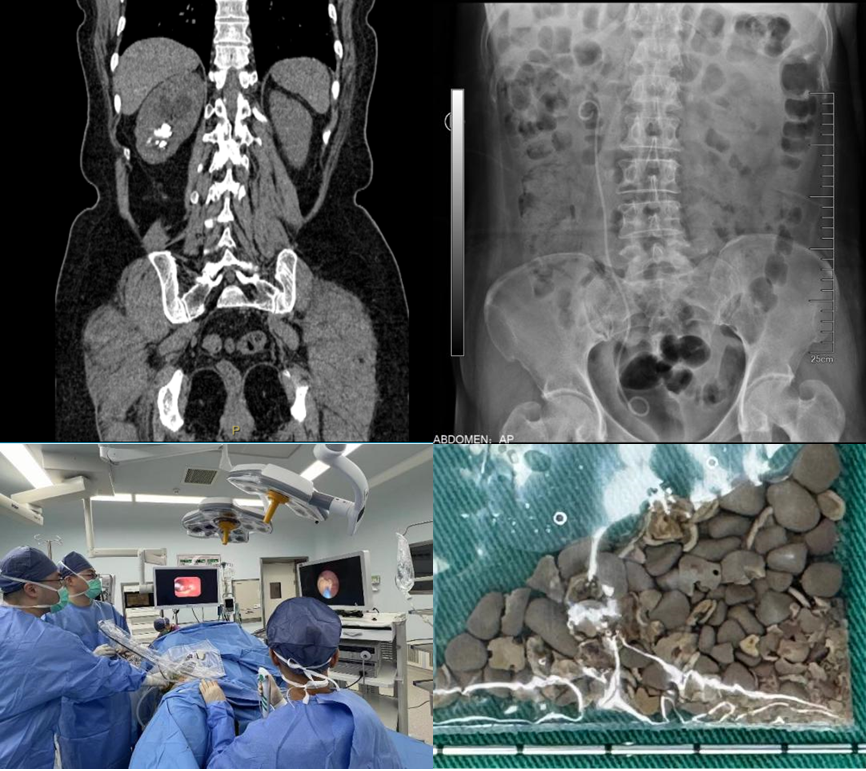

患者双肾结石多年,既往有多次结石手术病史,因为右腰部疼痛入院,检查后发现患者双肾多发结石。左侧为完全“鹿角型”结石,结石充满了整个肾脏,右侧输尿管也有多颗结石。浦金贤主任指出,患者双肾结石负荷大,左侧尤甚,且合并右侧输尿管结石,手术难度大,风险高,需优先保护肾脏功能,解除梗阻,尽可能彻底清除结石,减少术后再发概率。

经过科室讨论,周守军主任决定以分期手术的方式,借助智能控压清石系统,通过输尿管软镜处理右侧肾及输尿管结石。而对于左侧的无积水完全“鹿角型”结石,周主任在手术过程中一期采用标准通道经皮肾镜,结合第五代EMS超声弹道碎石系统清除结石主体,二期通过输尿管软镜配合末端可弯曲负压吸引鞘清除残余结石。术后患者恢复迅速,解决了困扰多年的结石问题。

患者在外院检查发现:CT提示右肾多发结石,右侧肾盂及输尿管扩张积水。患者既往曾多次行输尿管镜手术,存在右输尿管狭窄病史。患者入院后浦金贤主任组织科室讨论指出,患者右肾下盏多发结石,且部分位于下盏小盏,角度刁钻,手术难度大,单一经皮肾镜或输尿管软镜难以完全清除结石。周守军主任带领结石团队全力准备手术,采取斜仰卧位经皮肾镜-输尿管软镜(PCNL-RIRS)双镜联合的手术方式,一期手术彻底清除结石,复查结石无残留,达成理想的治疗效果。

该例患者2年来出现右腰部反复疼痛,伴尿频尿急尿痛、肉眼血尿。来我院前曾经在外院检查B超提示右肾结石,选择进行保守治疗并定期复查。近期患者再发右腰部疼痛来我院就诊,B超检查提示:右肾结石,右肾囊肿。尿常规检查提示:白细胞:1332/ul,予以口服抗生素治疗1周后收住入院。入院后进一步完善相关检查,CT检查提示:右肾结石,大小约3.1x1.8cm,右肾囊肿大小约5.0x3.5cm,复查尿常规:白细胞:191/ul。浦金贤主任带领科室成员仔细阅片后指出,患者结石位于肾盂输尿管连接处,负荷较大,且尿常规检查显示白细胞较高,考虑结石伴发感染可能性大,需严格控制感染,术中应注意肾盂内压力,减少术后严重感染风险。同时,患者右肾囊肿体积较大,可以考虑同次手术一并处理。根据患者病情特点,周守军主任采用腹腔镜微创手术的方式,一期手术同时行腹腔镜肾盂切开取石和腹腔镜肾囊肿去顶术,将结石完整取出、肾囊肿去顶减压,一次手术解决两个问题。患者术后迅速康复,未出现发热、尿瘘等并发症,顺利出院。